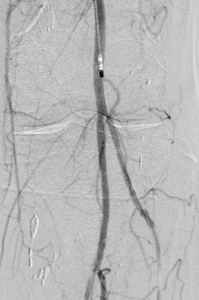

2. Angioplastie/ PTA – Gefäßweitung

Einengungen oder Verschlüsse von Gefäßen können durch Ballonkatheter beseitigt werden. Dazu werden die Ablagerungen in den Gefäßen zerteilt und in die Gefäßwand gedrückt, um so diese Stelle wieder zu glätten.

Neben sogenannten Normalballons kommen auch spezielle andere Arten von Ballonkathetern zur Anwendung. Dazu gehören u. a. Schneidballons oder Ballons die Stoßwellen abgeben, für sehr harte Gefäßablagerungen. Auch Ballonkatheter mit einer medikamentösen Beschichtung, die an die Gefäßwand abgegeben wird, um den arteriosklerotischen Gefäßumbau zu bremsen, werden eingesetzt.